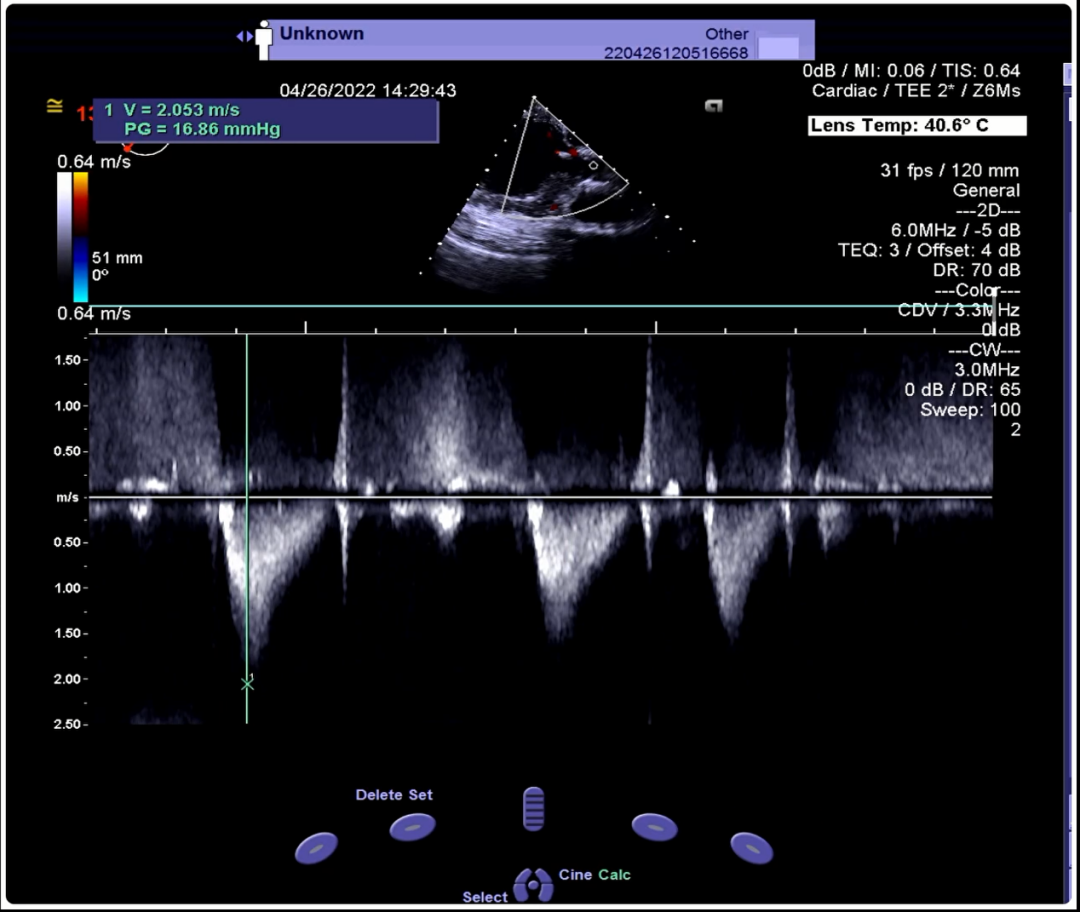

超声下血流动力学良好,无反流

术前V-max从4.1m/s下降至2m/s,PG 68mmHg下降至16.86mmHg。